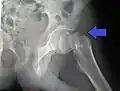

Mediale Schenkelhalsfraktur ohne Dislokation -

Laterale Schenkelhalsfraktur mit Adduktions-Dislokation -

Im Vergleich dazu ein gesundes Hüftgelenk